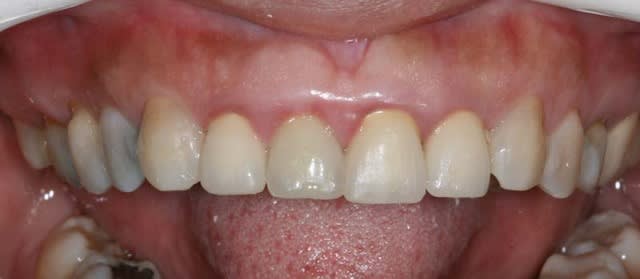

la CCM est en prov de luxe

(ça tombait bien,la teinte est moyenne,bien qu'elle passe mieux en bouche que sur la photo:le flash?)

la patiente part en vacances

je la referai en septembre

avec ou sans chir?...

il y a eu remodelage naturel(comme quoi entre la theorie et la clinique): peut on le considérer comme suffisant?

elle a une microdontie relative de ces insicives qui st maintenant redressées, alignées avec des diastèmes equidistants

et maintenant....

que feriez vous?

on comprend mieux la microdontie relative

les diastemes te genent? tu as peur de la recidive apres l'ortho?